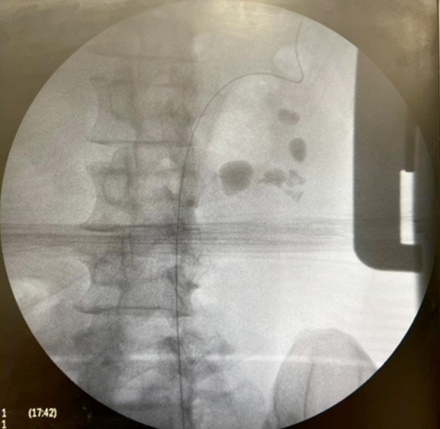

Sequência do tratamento:

-Tempo cirúrgico – 94 minutos

-Alta no 1oPO

-Retirada do Duplo J no 7o PO

-Eliminou vários pequenos fragmentos

-TC com 30 dias – livre de cálculo